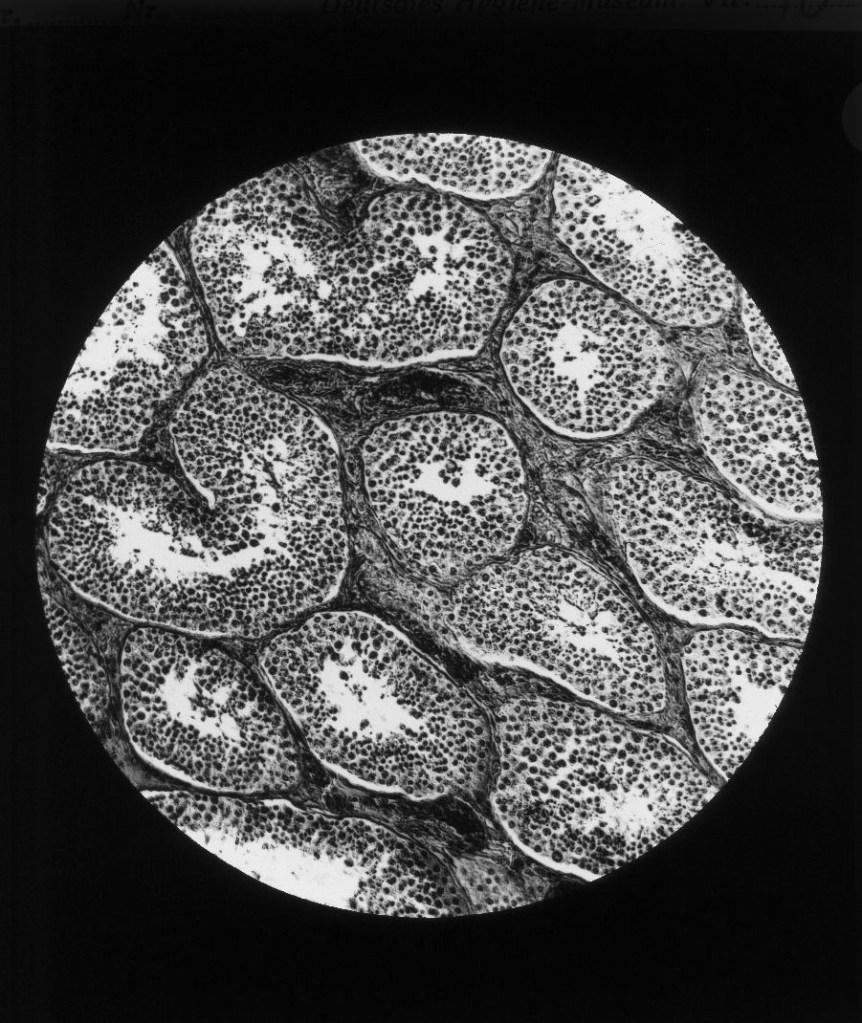

Auch mikroskopische Darstellungen wurden gezielt eingesetzt, um naturwissenschaftliche Erkenntnisse und medizinische Theorien über die Gefahren des Alkoholkonsums für die Allgemeinheit sichtbar zu machen.

Geschrumpfte Hodenkanälchen, „Degeneration“ und „entartete“ Nachkommenschaft

Gustav von Bunge (1844–1920), Basler Physiologe und ein prominenter Vertreter der wissenschaftlich geführten Abstinenzbewegung, postulierte, ausgehend vom degenerationstheoretischen Gedanken, dass der weit verbreitete Alkoholismus nicht nur den trinkenden Individuen schade, sondern eine Bedrohung der Gesellschaft darstelle, die in einer „Degeneration“ des „Volkes“ münden würde. Man bekämpfte also nicht den individuellen Alkoholismus, sondern die kollektive „Volkskrankheit“. Alkoholiker wurden so als „minderwertige“ Menschen denunziert, die mit ihrem „entarteten“ Erbgut den „Volkskörper“ schwächen. Medizinisch-mikroskopische Darstellungen liefern dafür den Beleg.

Querschnitt durch Hoden

Querschnitt durch Hoden bei einem 20järigen Trinker. (nach einem mikr. Originalpräparat von Prof. Weichselbaum). Keimgewebe entartet, zwischen den geschrumpften Hodenkanälchen massenhaft Bindegewebe.